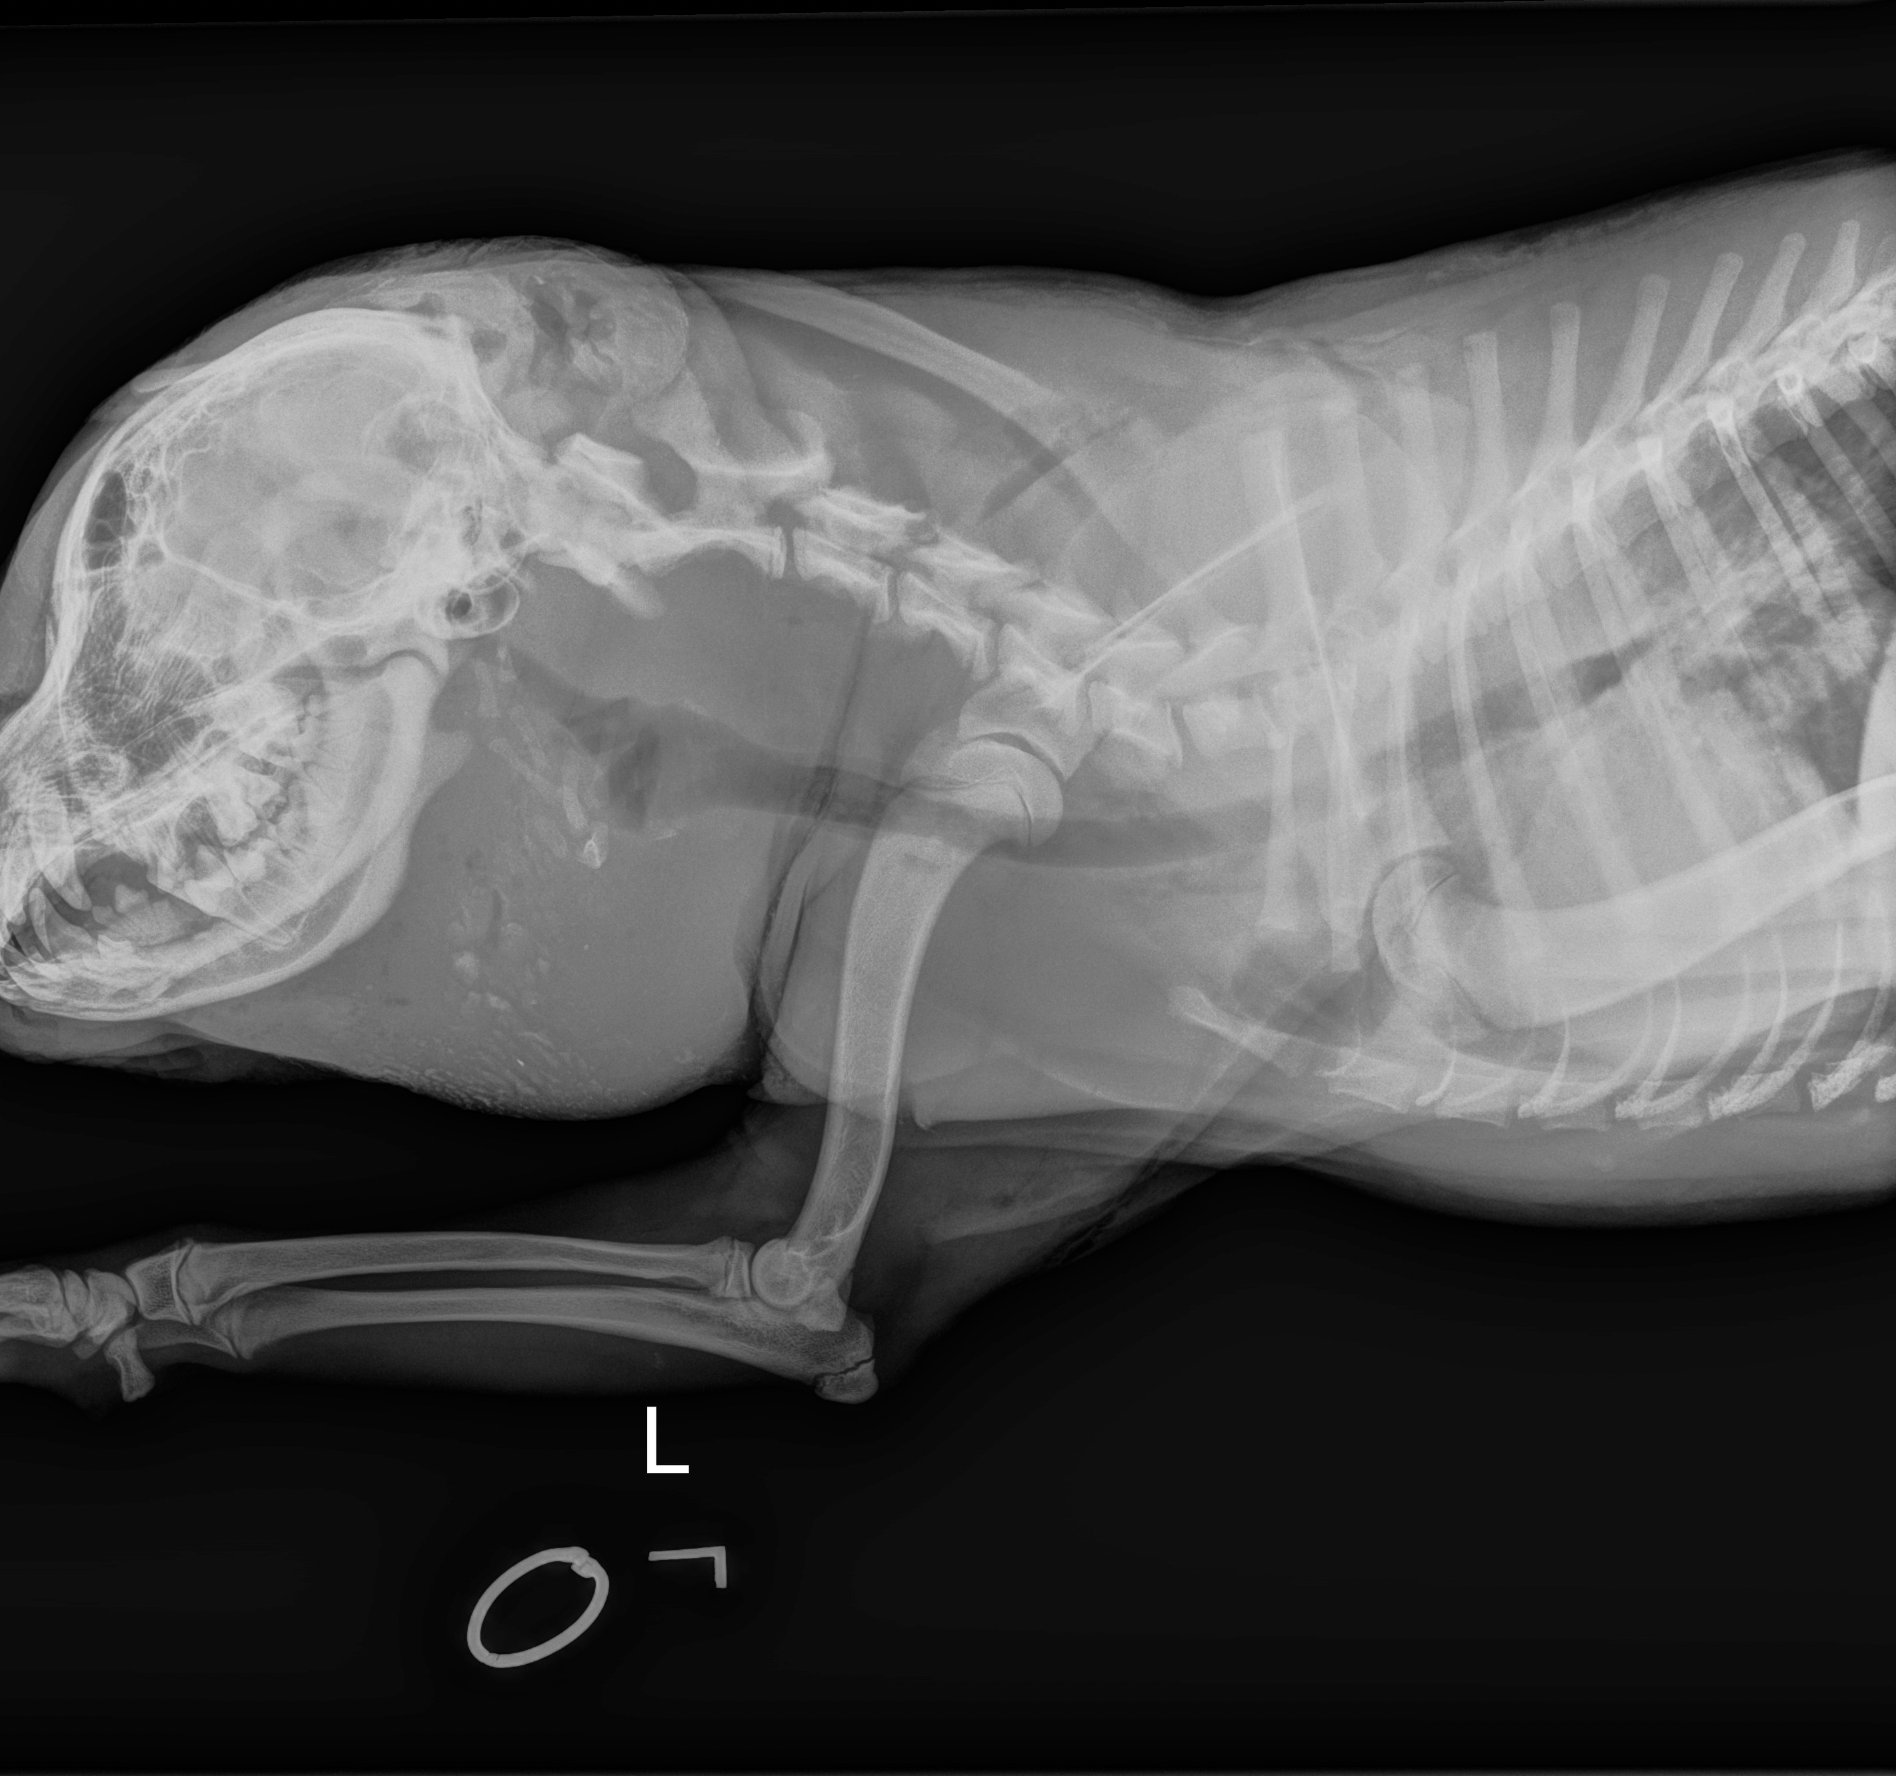

Once Jessie was stabilized and sedated, her wounds were carefully cleaned. That’s when the full truth emerged—revealed by X-rays that told a story her body had been silently holding.

The damage was severe. The bone beneath her eye—the orbital bone—was completely shattered. Several teeth on the same side were broken down to their roots. While the worst injuries were concentrated on one side of her face, hidden wounds were also discovered behind her ears and across the top of her head.

What baffled the medical team was what wasn’t there. No bullet fragments. No injuries to her legs or torso. Whatever caused this trauma seemed focused solely on her head, deliberate and brutal.